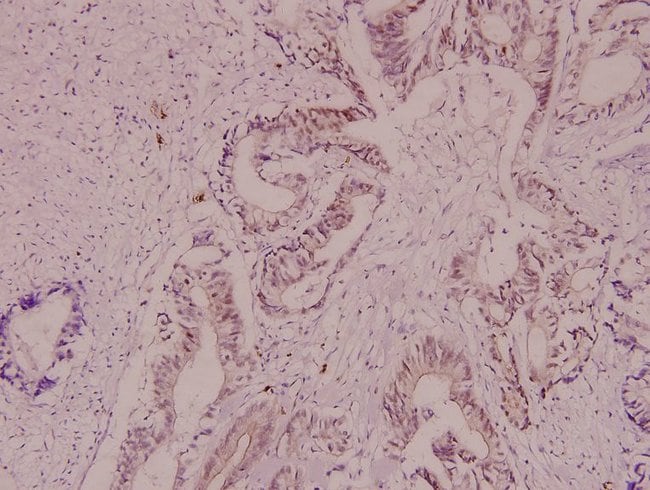

Invitrogen™ CRYAB Polyclonal Antibody

Immunohistochemistry (Paraffin)